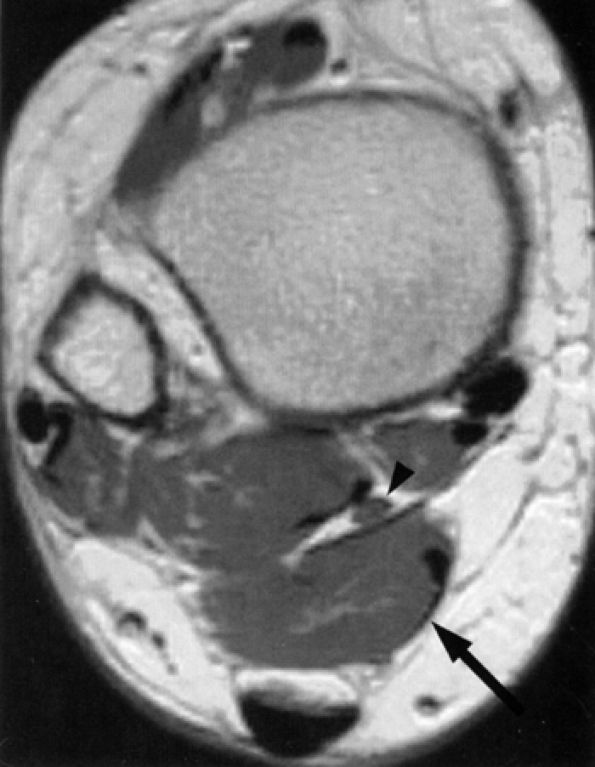

In our experience, incidental MR detection of denervation edema and atrophy of the abductor digiti quinti muscle is not uncommon and most likely reflects a clinically missed entrapment of the first branch of the lateral plantar nerve (Figs. 6.55 and 6.56).

FIGURE 6.55 ● Neuropathy of the inferior calcaneal nerve (Baxter's neuropathy). Coronal T1-weighted image of the ankle demonstrating denervation atrophy of the abductor digiti quinti (arrow). Note metallic susceptibility artifact secondary to a distal fibular fixation plate and screws.

|

FIGURE 6.56 ● Neuropathy of the inferior calcaneal nerve (Baxter's neuropathy) in a 66-year-old patient with tarsal tunnel varicosities. Sagittal (A) and axial (B) T1-weighted images of the ankle demonstrate denervation atrophy of the abductor digiti quinti muscle (asterisk). (C and D). Normal abductor digiti quinti muscle (asterisk) in an asymptomatic patient for comparison.